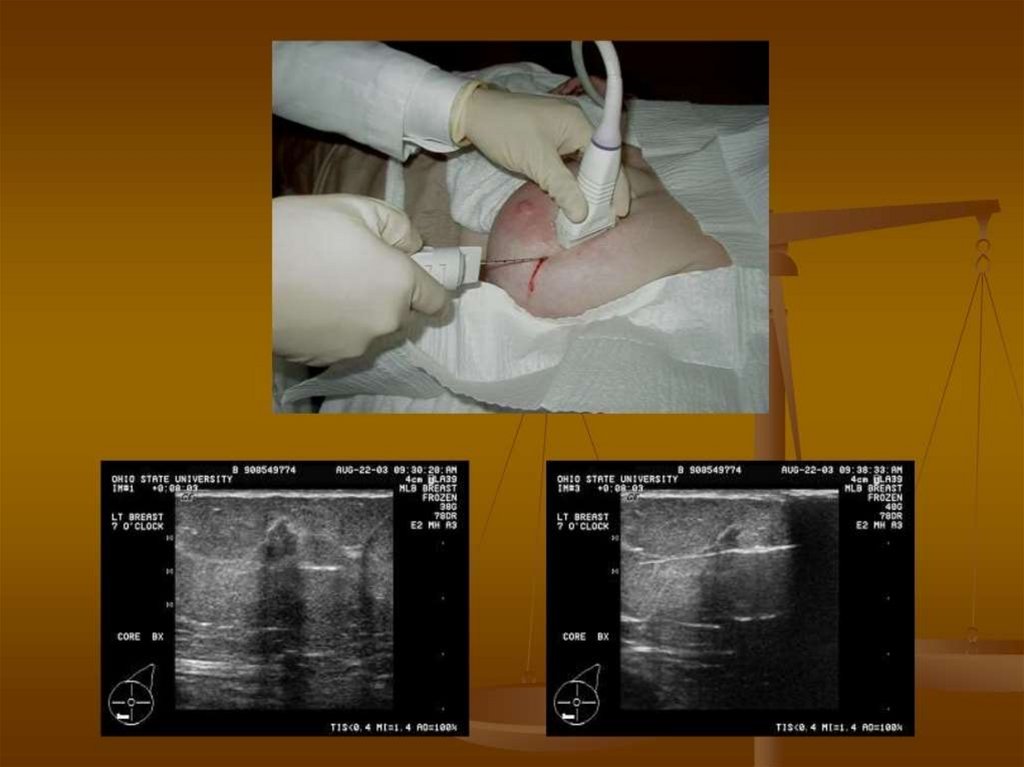

Benign Breast Disease